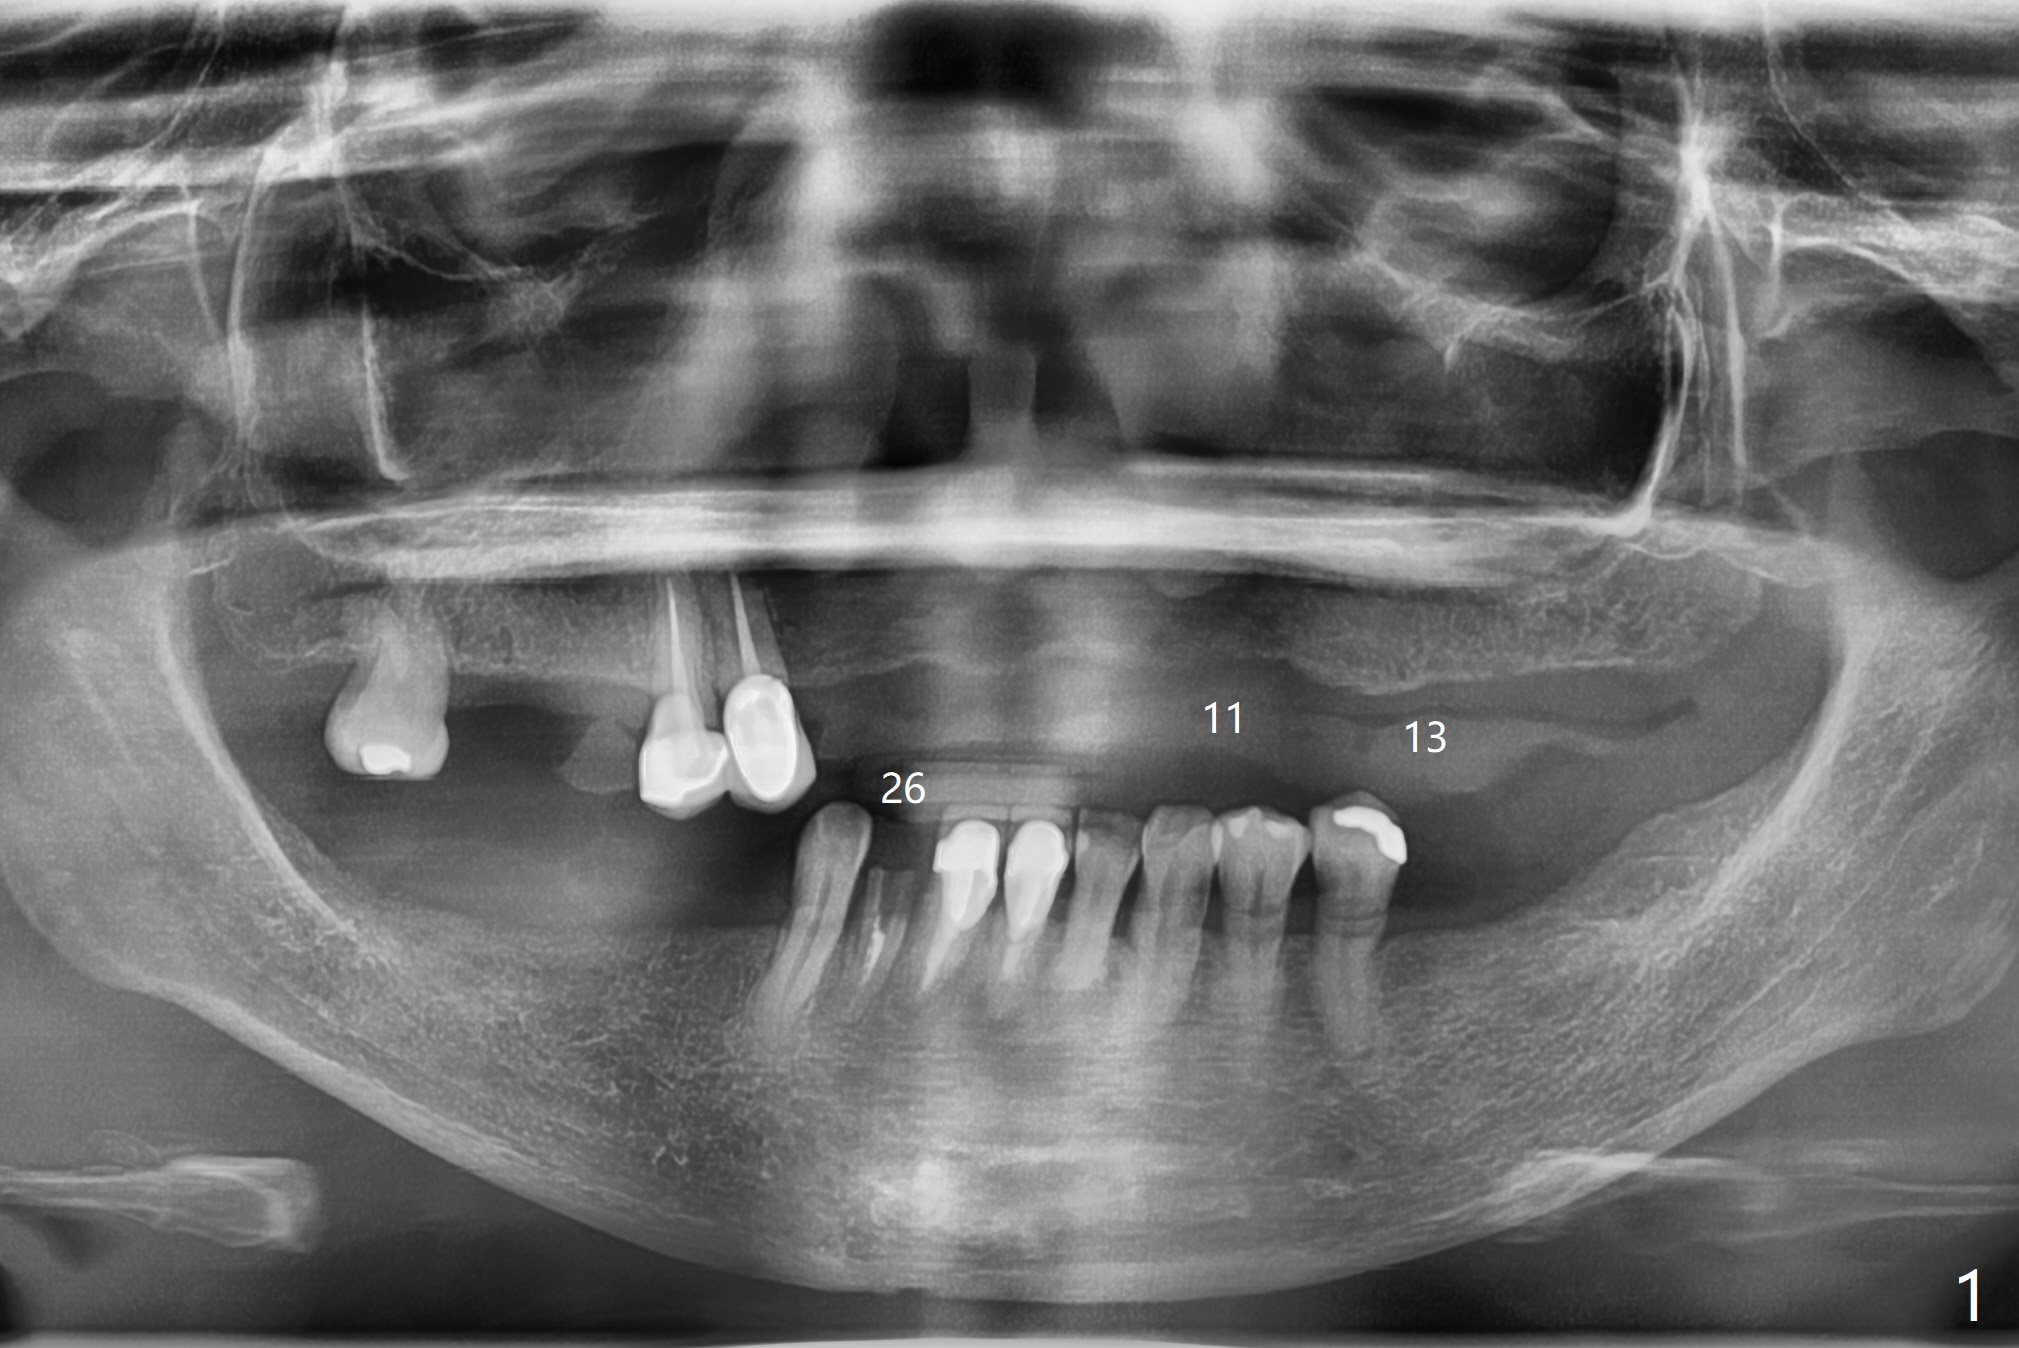

A 63-year-old woman presents to clinic with fractured crown/post at #26 (Fig.1). After recementation of the crown, the upper Valplast RPD is found to be unstable. After discussion, she agrees to have two implants and ball abutments at #11 and 13 for retention. Use pink acrylic to fixate a denture tooth of #3 to the Valplast. Alginate impression (upper and lower jaws with RPDs and upper without RPD) will be taken to make radiographic stent (Barium Sulfate). With the latter, take small field CT (5x5 cm) to decide the size of the implants. After implant and ball abutment placement, soft reline the Valplast until osteointegration. When Barium Sulfate and Jet are mixed with monomer, the mixture is applied to tissue surface of #11-13 of the upper Valplast. CT is taken. The latter shows that the bone at #11 is thin, while the bone at #14 is short. The sites of #12 and 13 are proper for implant placement (Fig.2,3).